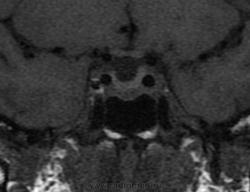

Ж, 37 лет. Наблюдается по поводу микроаденомы гипофиза, исследование в динамике. Предыдущие снимки сделаны в другом учреждении около года назад, картинка примерно такая же, однако на пленке отсроченные и постконтрастные снимки отсутствуют. В заключении была обозначена микроаденома округлой формы 3мм в диаметре.

Вот такая интересная картинка у нас получилась:

T1

T2

Динамика (25, 50, 75, 90с.):

Постконтрастные:

И, наконец, отсроченные через 15 минут:

А, гипофиз, что, полупустой?

Не полупустой, в нижних отделах странной формы аденома. Плоская какая-то. За аденому то, что она хоть и медленно, но накапливает контраст, который в ней задерживается после того, как уже почти полностью вымылся из здоровой паренхимы аденогипофиза. Полупустой гипофиз (вернее полупустое турецкое седло, ещё вернее вторично "пустое" турецкое седло) получается после удаления аденомы. Или после самопроизвольного опорожнения кисты/кистозной аденомы гипофиза. 2 часа назд такое контролировал.

Честно говоря, я сначала подумал, что гипофиз как будто "висит" над дном турецкого седла, а под ним - жидкость. После контрастирования действительно - аденома.

Нет, оказалось, что это вовсе не жидкость, а по характеру накопления парамагнетика - аденома необычной формы и локализации.